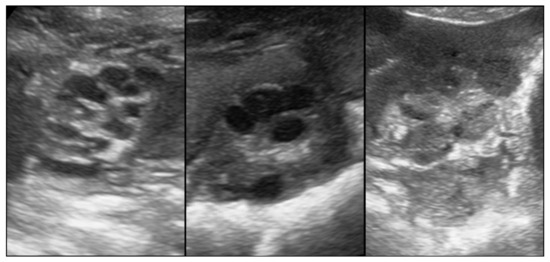

- Kauffold, J.; Rautenberg, T.; Richter, A.; Waehner, M.; Sobiraj, A. Ultrasonographic characterization of the ovaries and the uterus in prepubertal and pubertal gilts. Theriogenology 2004, 61, 1635–1648. [Google Scholar] [CrossRef]

- Vela, A.; Suárez-Usbeck, A.; Lafoz, L.; Mitjana, O.; Tejedor, M.T.; Martín, S.; López, M.; Falceto, M.V. Determination of puberty in gilts: Contrast of diagnostic methods. Porcine Health Manag. 2022, 8, 28. [Google Scholar] [CrossRef] [PubMed]